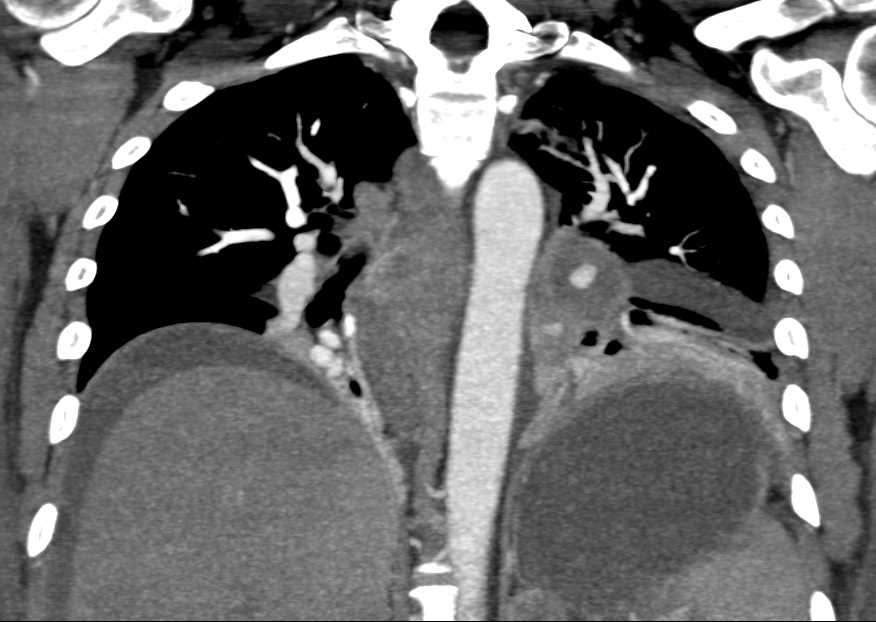

Pulmonary Artery Pseudoaneurysm